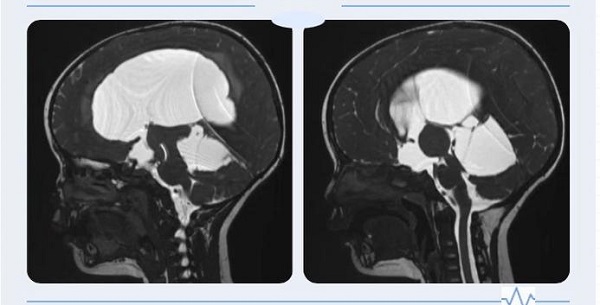

一岁多的赫赫自出生头颅就比同龄小孩大,近半月来进食后出现呕吐、头痛,哭闹不止,在省内多处求医未果,最终慕名来到二一五医院神外重症监护室就诊,行磁共振检查后诊断为“梗阻性脑积水”。 经过严密的术前评估及...